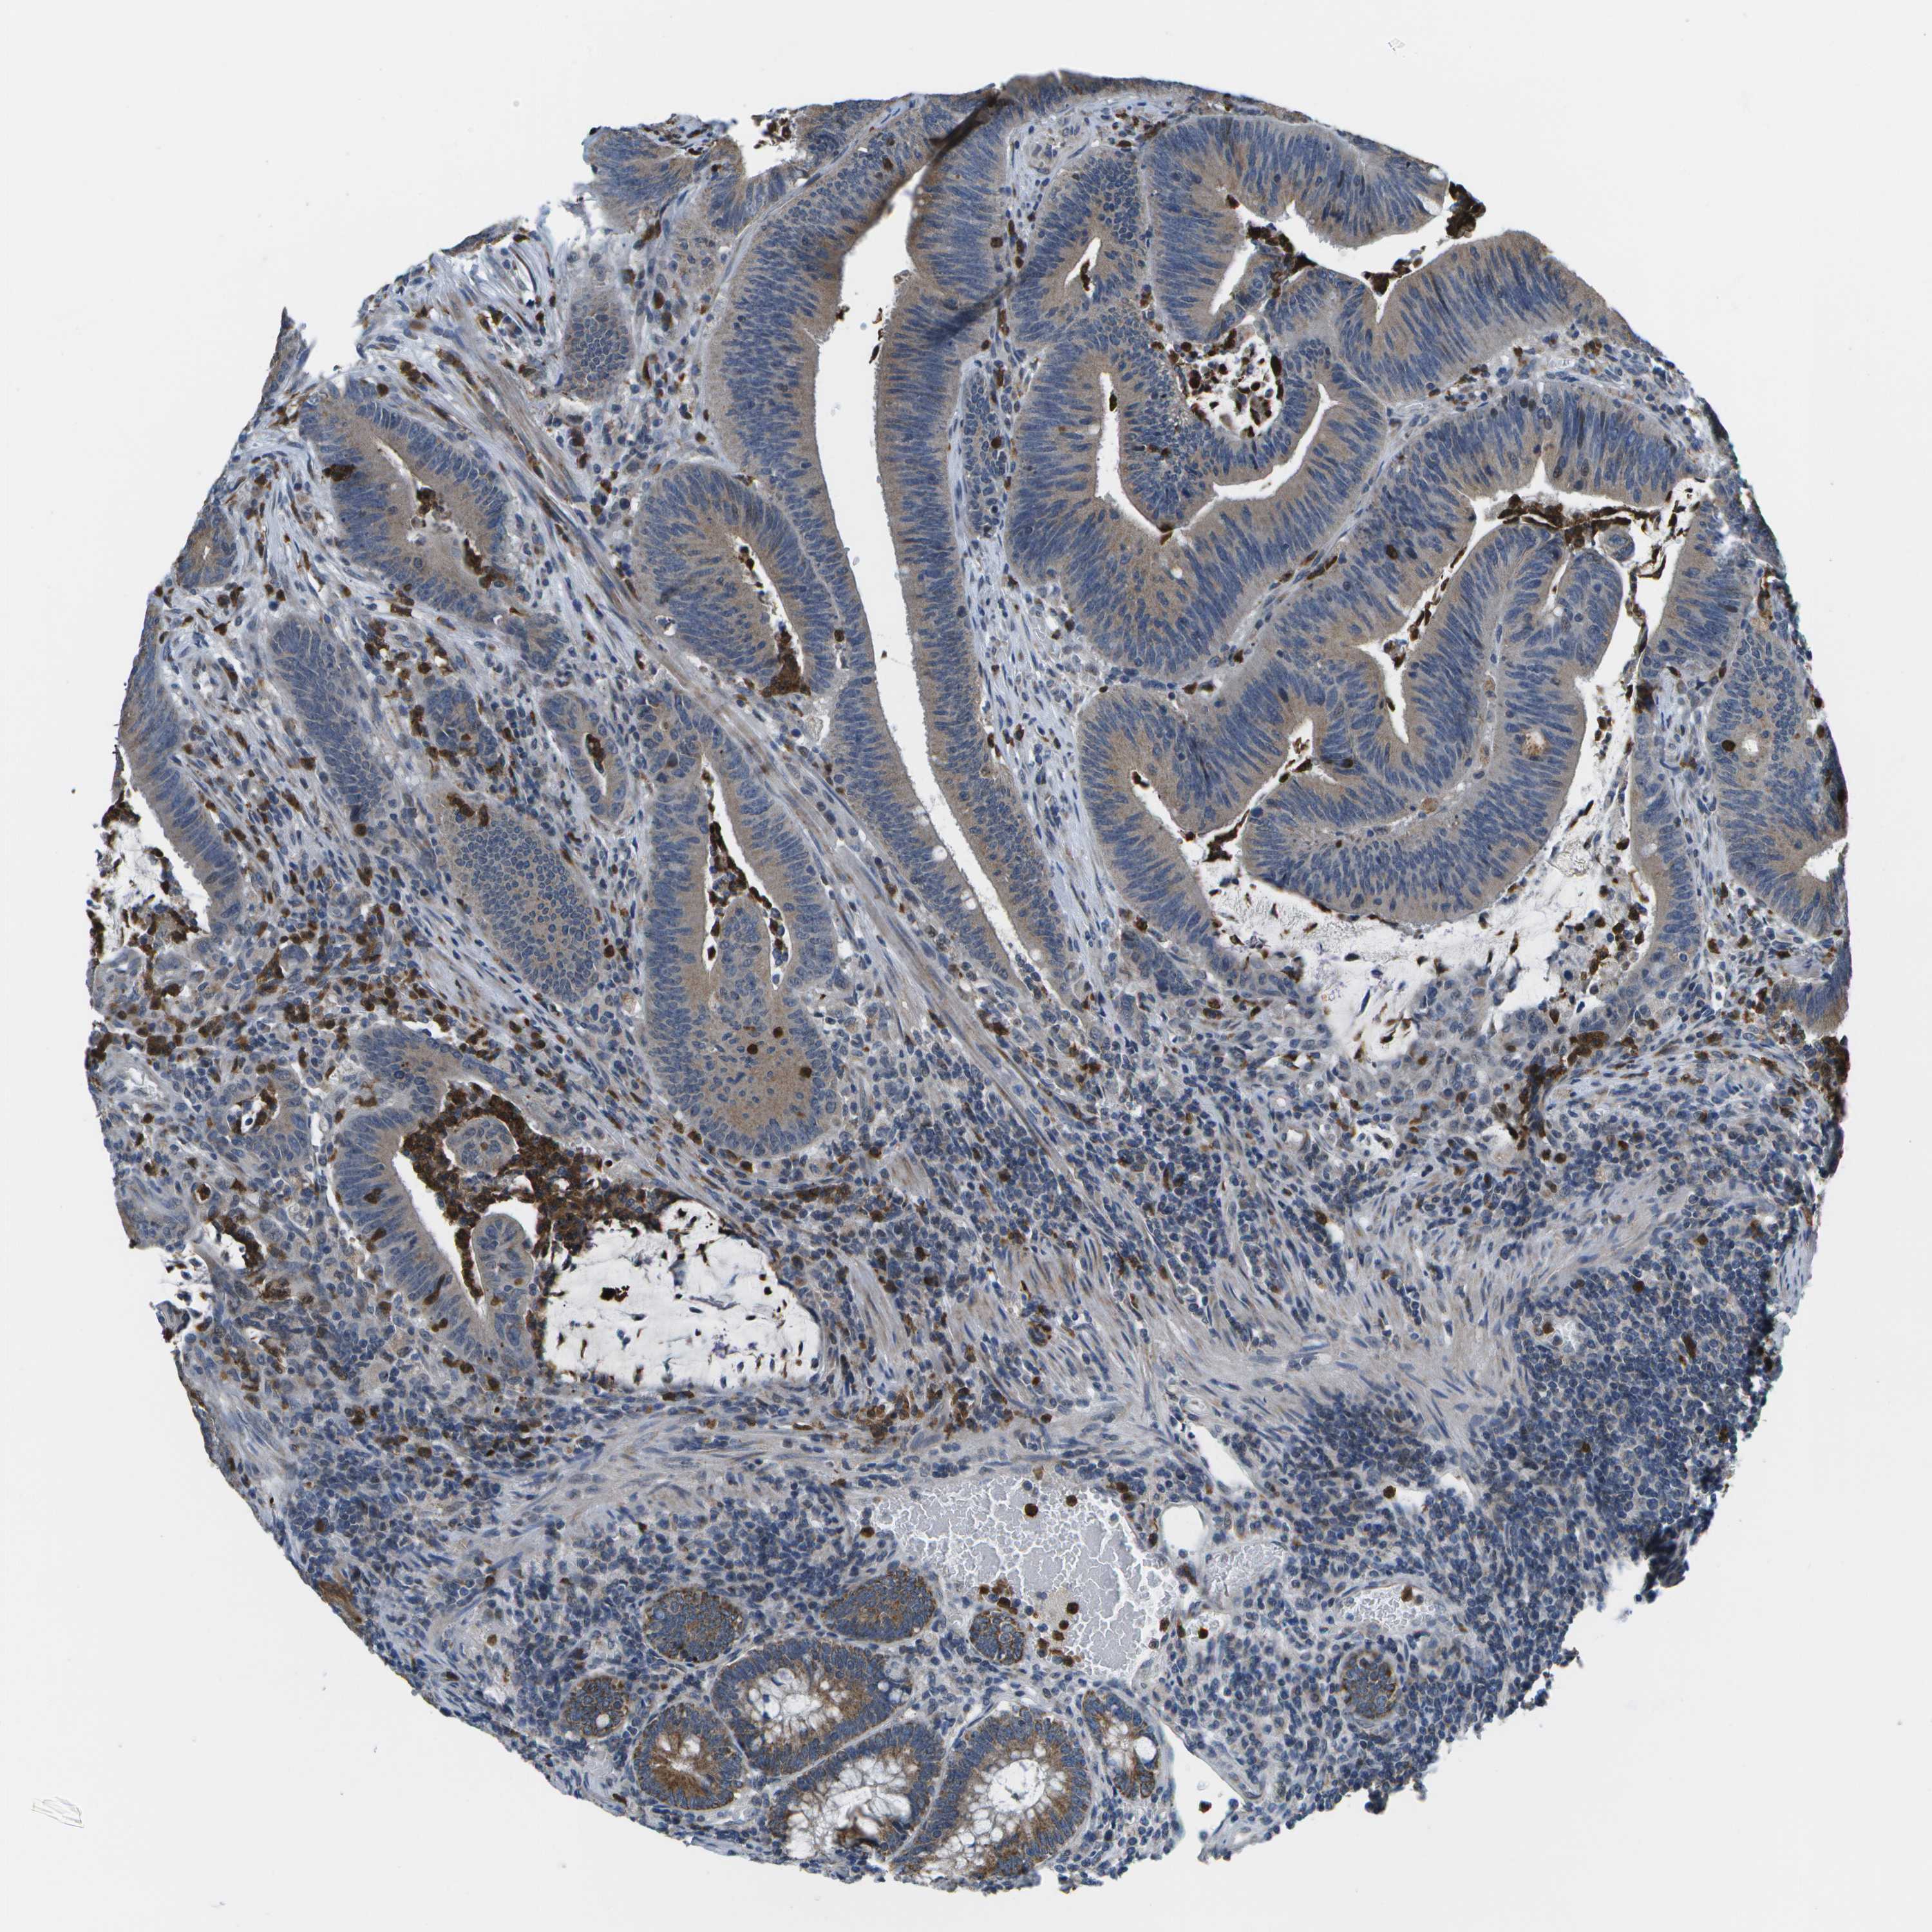

CANCER COLORECTAL CANCER Show tissue menu

Colorectal cancer

Human cancer

Colon adenocarcinoma